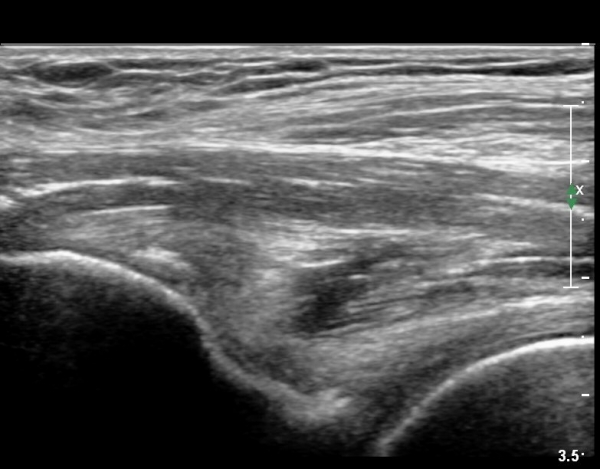

ÃÊÀ½ÆÄ °Ë»ç